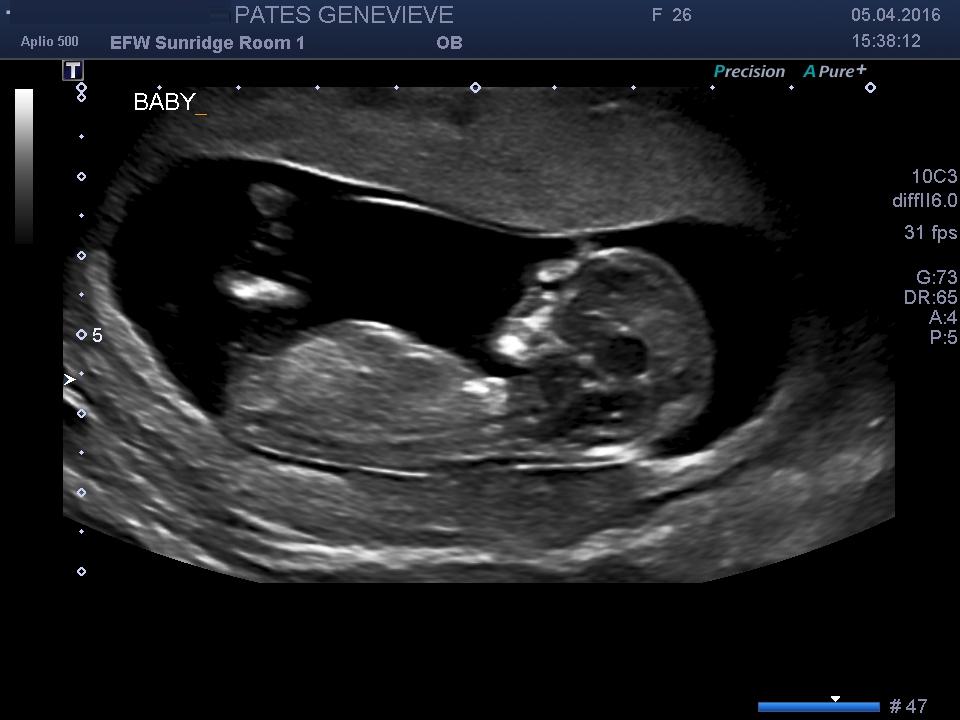

Can anyone say is it boy or girl looking to skullAttachment 30656

Boy